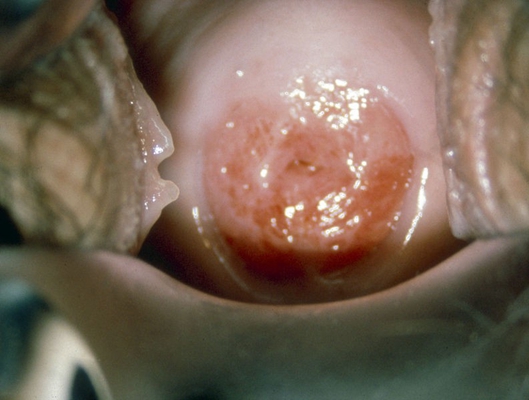

子宮頸癌圖片

宮頸癌

宮頸癌

宮頸癌

宮頸癌

宮頸癌

宮頸癌

宮頸癌

宮頸癌

宮頸癌

宮頸癌

宮頸癌

宮頸癌

宮頸癌

宮頸癌

宮頸癌

宮頸癌

宮頸癌

宮頸癌

宮頸癌

宮頸癌